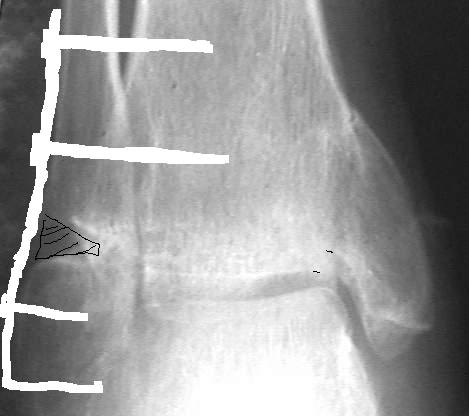

У больного травма в августе 2001 г. Лечился консервативно, Проводилась иммобилизация гипсовой лонгетой 3 мес. В последующем местное лечение. Остается контрактура боли в области наружной лодыжки. Направлен в наше отделение в конце января 2002 г Планируется костная аутопластика, остеосинтез пластиной, винтами перелома наружной лодыжки. Решается вопрос о коррекции неправильно сросшегося перелома внутренней лодыжки. Рентгенограммы: фас; профиль; план Сергей Зырянов

Насчет наружной лодыжки - не уверен, что вообще надо что-то делать.

на снимке, кстати, срезан ее дистальный отдел, и правильность взаимоотношений с таранной костью не оценить. Если они правильные - я бы присоединился к мнению об оставлении ее покое.

А вот укорочение внутренней, похоже, привело к натяжению дельтовидной связки и гиперпрессии в медиальном отделе сустава, и уже сейчас там

видно сужение щели. Так что есть смысл обратить внимание на ортопедическую профилактику деформирующего артроза.

Коллеги! Я думаю надо плясать от возраста, профессии, объёма движений и интенсивности болевого синдрома. Ничего подобного не прозвучало... Имеет место подвывих стопы кнутри, никем не отмеченный! Оно конечно варус лучше, чем вальгус, но в данном случае принципиально его устранение (если оперировать конечно). Если оперировать, то предлагаю:

1. Остеотомию и низведение внутренней лодыжки. Фиксация винтом или пучком спиц.

2. Остеотомию наружной лодыжки и фиксация компрессирующим винтом (при необходимости дополнить аутокостью). Винт должен быть достаточно длинным дабы соблюдать ось!

Данными манипуляциями устраняем подвывих стопы, гиперпрессию дельтовидной связки и пытаемся устранить ложный сустав наружной лодыжки (существование которого весьма сомнительно). Но судя по снимкам щель сустава уже возможно заполнена рубцом, либо капсула сильно рубцово изменена и нормализация движений в п/о периоде сомнительна. Так, что попробовать конечно можно, но нужно ли.